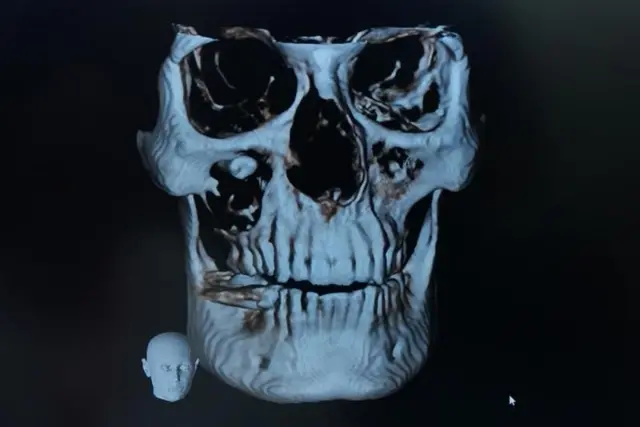

માનવખોપરીમાં જ્યાં આપણી આંખ સ્થિત હોય છે એ બોન સેલને ઑર્બિટ કહે છે. સરળ શબ્દોમાં કહીએ તો આંખને ચારેકોરથી રક્ષણ પૂરું પાડતું સૉકેટ જ ઑર્બિટ છે.

આંખના નીચેના ભાગના ઑર્બિટને 'ફ્લોર ઑફ ધ ઑર્બિટ' કહેવાય છે.

દર્દી રમેશકુમારે જ્યારે સીબીસીટી કરાયા બાદ ખબર પડી કે ફ્લોર ઑફ ધ ઑર્બિટમાં દાંતનાં મૂળ છે.

પ્રિયાંકર કહે છે કે, "આ મામલામાં દાંતનાં મૂળ ફ્લોર ઑર્બિટમાં હતાં. જ્યારે તેનો ક્રાઉન પોર્શન (દાંતનો સફેદ ભાગ) મૅક્સિલરી સાઇનસમાં હતો. આ દાંત પોતાની નૉર્મલ જગ્યાએ નહોતો બન્યો તેથી શરીર માટે એ ફૉરેન બૉડી હતો."

મૅક્સિલરી સાઇનસ, ફ્લોર ઑફ ધ ઑર્બિટ અને આપણા ઉપરના ભાગના જડબાની વચ્ચેનો ભાગ છે. સરળ શબ્દોમાં આ ગાલનો એક ભાગ છે.

દાંત આંખના ફ્લોર ઑફ ધ ઑર્બિટમાં ઊગી રહ્યો હતો, તેથી જ્યાંથી ઘણી બધી નસો નીકળે છે, તેથી આ એક મુશ્કેલ સર્જરી હતી.